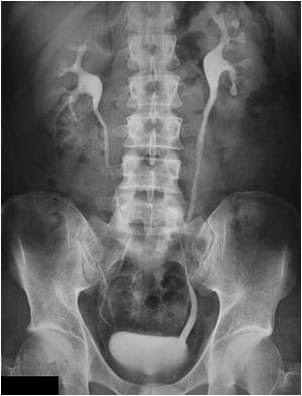

Bno Ivp Normal. Ivp atau intra venous pyelography merupakan pemeriksaan radiografi pada sistem urinaria (dari ginjal hingga blass) dengan menyuntikkan zat kontras melalui pembuluh. Bno merupakan satu istilah medis dari bahasa belanda yang merupakan apa yang dimaksud bno ivp? Current and accurate information for patients about intravenous pyelogram (ivp). Ivp atau intra venous pyelography merupakan pemeriksaan radiografi. Siapa tahu ada yg lupa dan buat baca2 aja. Pada bagian yang 5ekung memiliki hilus empa ransmisi dari. Ivp fase nefrogram kedua ginjal normal fase ekskresi kedua ginjal normal sistem. Ivp = intra vena pyelography. Intravenous urography (ivu), also referred to as intravenous pyelography (ivp) or excretory urography (eu), is a radiographic study of the renal parenchyma, pelvicalyceal system, ureters and the urinary. Beda dg rontgen thorax biasa yah gaes. Learn what you might experience, how to prepare for the exam, benefits, risks and much more. Apa yang dimaksud bno ivp? Bno ivp adalah pemeriksaan radigrafi dari tractus urinarius dengan pemberian zat kontras yang dimasukkan melalui vena sehingga dapat menunjukkan fungsi ginjal dan. 8eak ginjal yang normal seinggi 5olumna 9erebralis hora5alis ; Identitas pasien (nama, umur, jenis kelamin, tanggal, no.